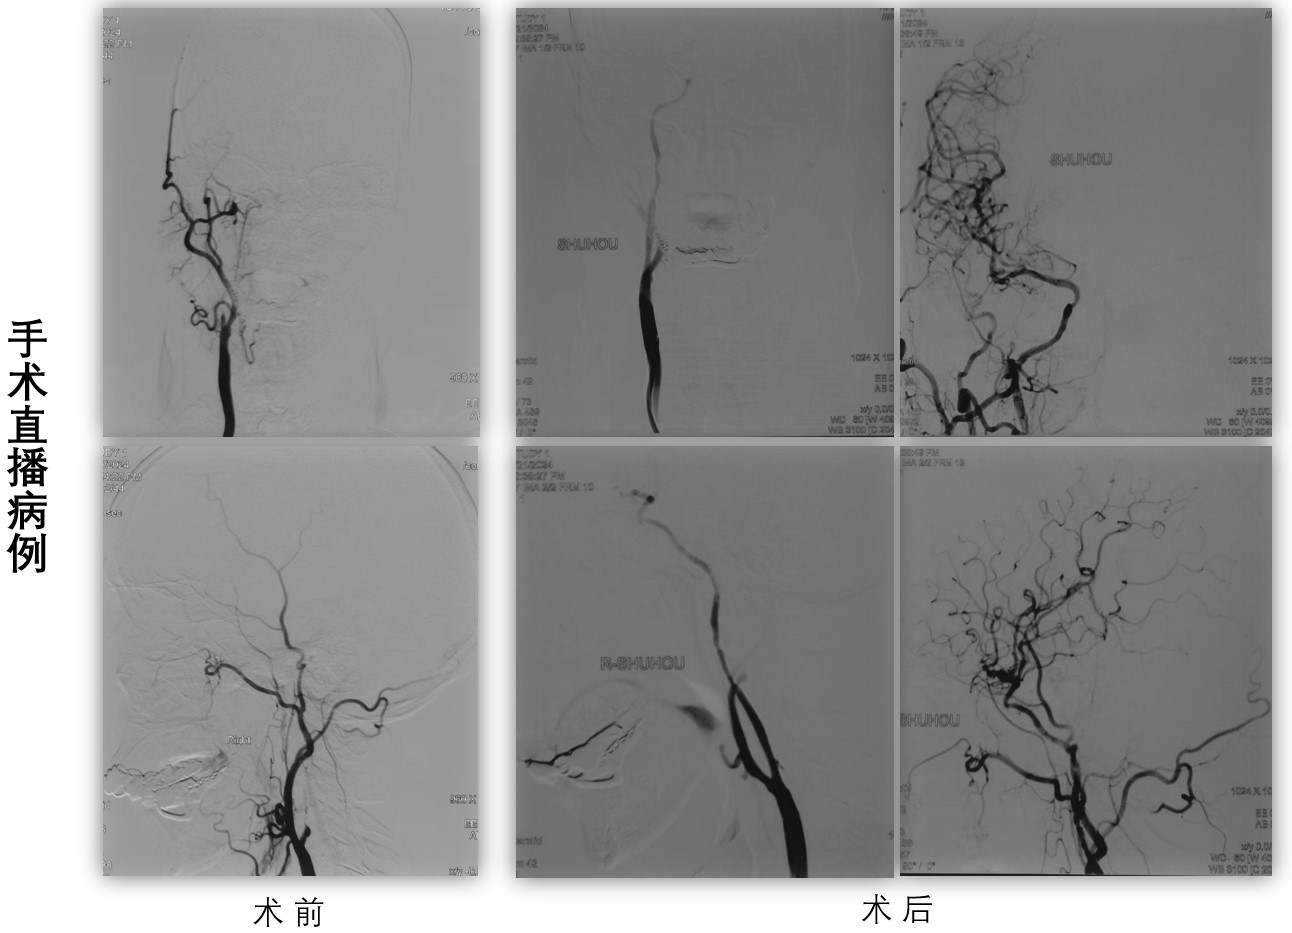

在本次手术直播期间,我院神经内科张茹副主任、吴海琴教授、王虎清教授带领神经介入团队樊洪、范清雨、高震、范松华、张磊、张宏等年轻一代介入医生成功完成急性脑梗死机械取栓、颈动脉支架置入等5台精彩的手术直播演示,获得外院专家及线上同道一致好评,手术过程中各位专家围绕取栓策略、颈动脉狭窄支架置入术材料选择、围术期血压及心率管理等方面进行了热烈讨论,分享各自的手术经验、技巧,此次手术直播演示共吸引了近4000人观看,对进一步推动缺血性脑血管病介入手术安全、规范的开展发挥了积极作用。